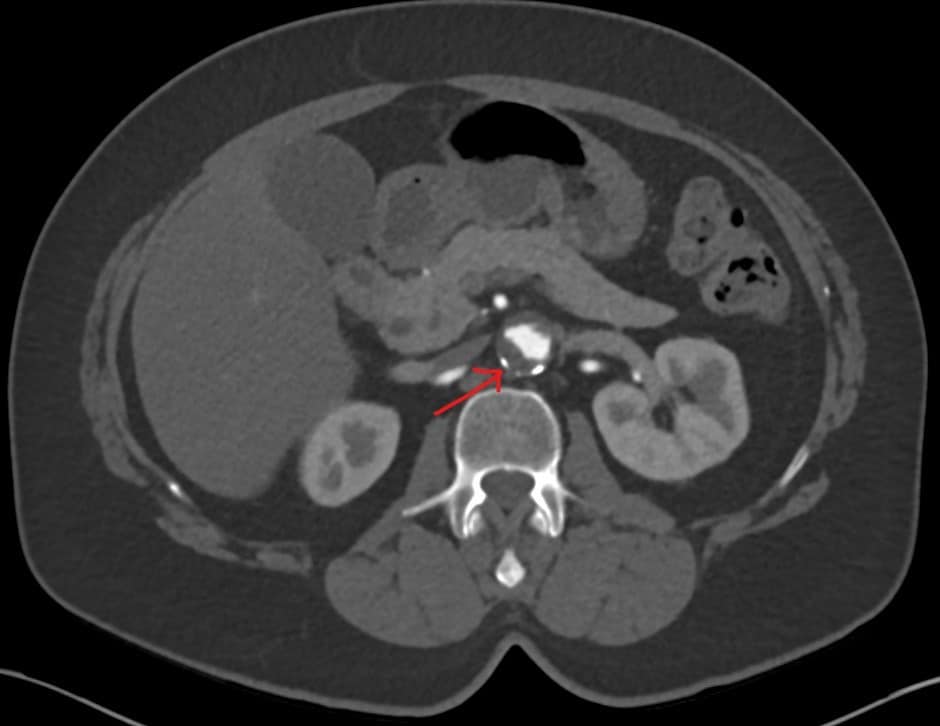

Mural thrombus

Mural thrombus in a small aortic aneurysm